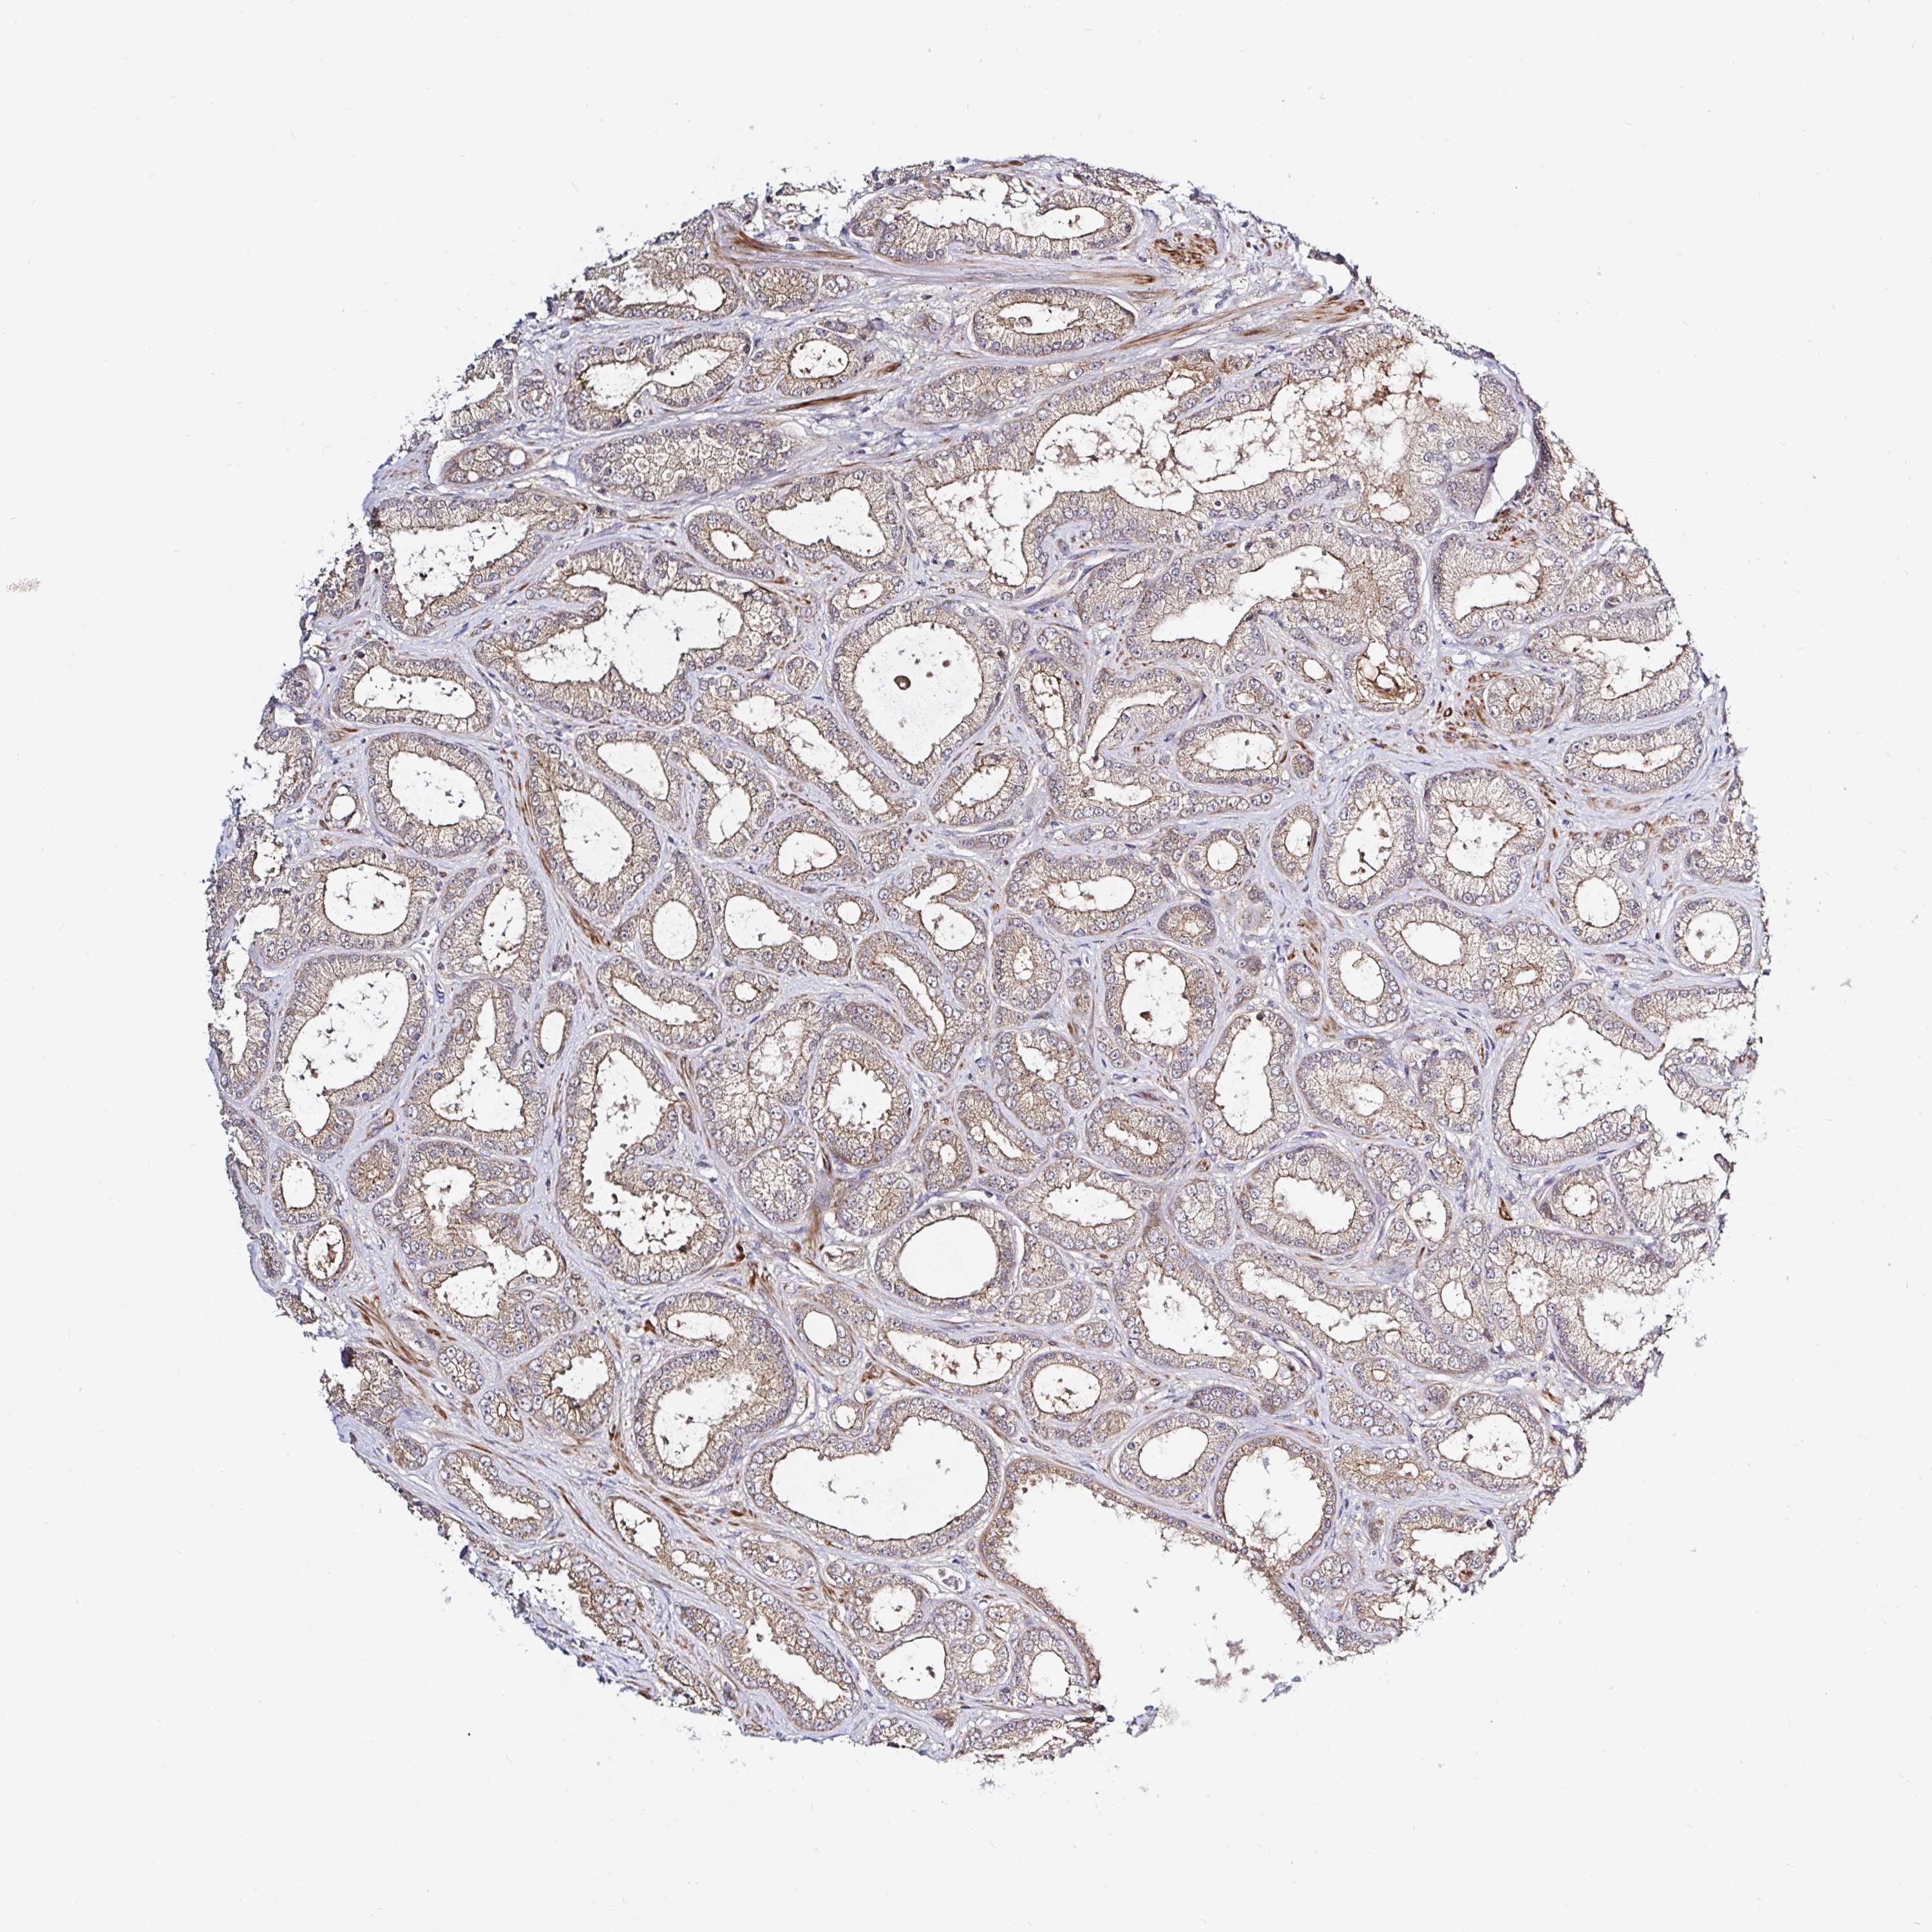

PROSTATE CANCER - Protein expressioni

A mouse-over function shows sample information and annotation data. Click on an image to view it in a full screen mode. Samples can be filtered based on level of antibody staining by selecting one or several of the following categories: high, medium, low and not detected. The assay and annotation is described here.

Note that samples used for immunohistochemistry by the Human Protein Atlas do not correspond to samples in the TCGA dataset.

Antibody stainingi

Antibody staining in the annotated cell types in the current human tissue is reported as not detected, low, medium, or high, based on conventional immunohistochemistry profiling in selected tissues. This score is based on the combination of the staining intensity and fraction of stained cells.

Each image is clickable and will lead to virtual microscopy that enables deeper exploration of all samples and also displays staining intensity scores, fraction scores and subcellular localization as well as patient and tissue information for each sample.

Antibody HPA043885

Antibody HPA053487

Staining

High

Medium

Low

Not detected

Intensity

Strong

Moderate

Weak

Negative

Quantity

>75%

75%-25%

<25%

None

Location

Nuclear

Cytoplasmic/membranous

Cytoplasmic/membranous,nuclear

Adenocarcinoma, NOS

Adenocarcinoma, High grade

Adenocarcinoma, Low grade